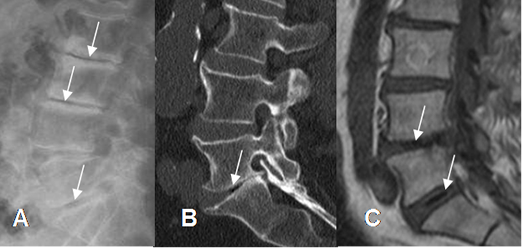

Fig 34. Fenómeno del vacío.

A: Rx lateral, B: TAC reconstrucción sagital y C: RM sagital en T1. Presencia de aire dentro de los discos, por proceso degenerativo.